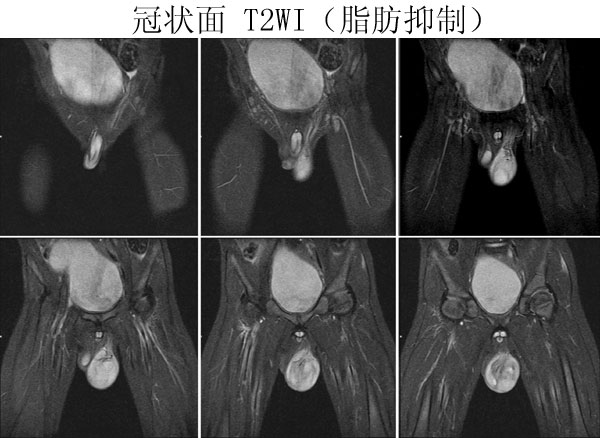

(广东同江医院的病例)男,2岁。左侧睾丸肿大3月,开始发现时红枣大,逐渐增大,现鸡蛋大小,表面光滑,无压痛,质地中等。

病理诊断 :(左侧)

睾丸胚胎性横纹肌肉瘤

,瘤组织局部浸润附睾组织,精索残端组织内未见瘤组织浸润。